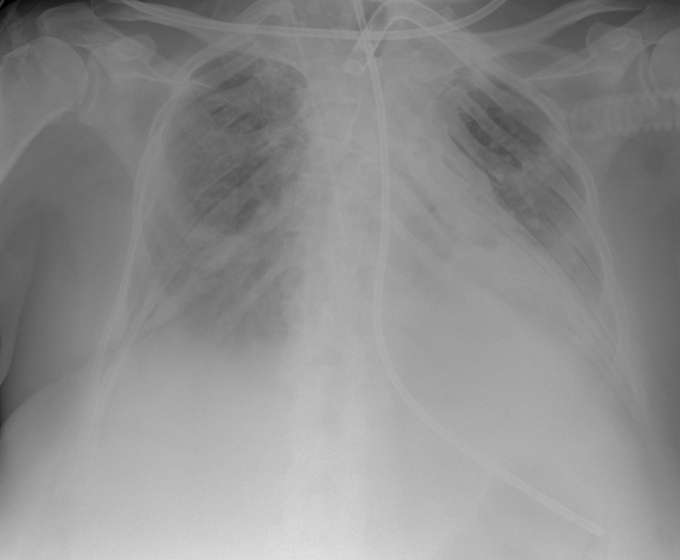

Series: 01022001

1. Series: 01022001

Was prädisponiert diesen Patienten für entzündliche Lungenkrankheiten?